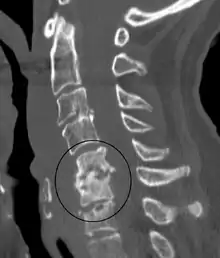

| Discitis in a 2 year old child. | |

Diagnosis is usually apparent on MRI although plain X-rays and CT examinations can be suggestive. The MRI will reveal air changes in the disc and possibly even external involvement involving the bone or epidural regions. A biopsy may be performed and helps with diagnosis in some cases but often an organism is not obtained. C-reactive protein levels and ESR levels will be elevated and are useful for treatment. Often, the white blood cell count will be normal and the patient will be afebrile.